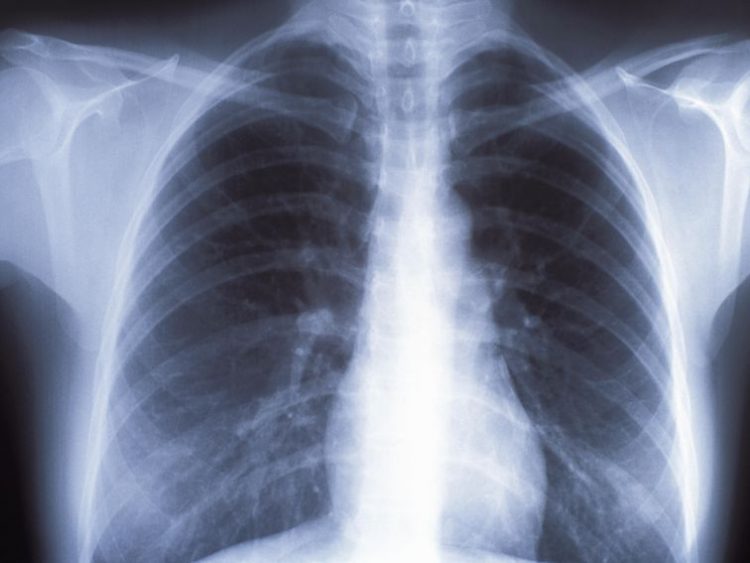

The number increased significantly from 2018, which coincides with Microsoft ending support for Windows 7 earlier this year. A significant number of machines run even older operating systems, including Windows XP, which Microsoft stopped supporting in 2014. The imaging devices include machines that take X-rays, MRIs, mammograms and CAT scans.